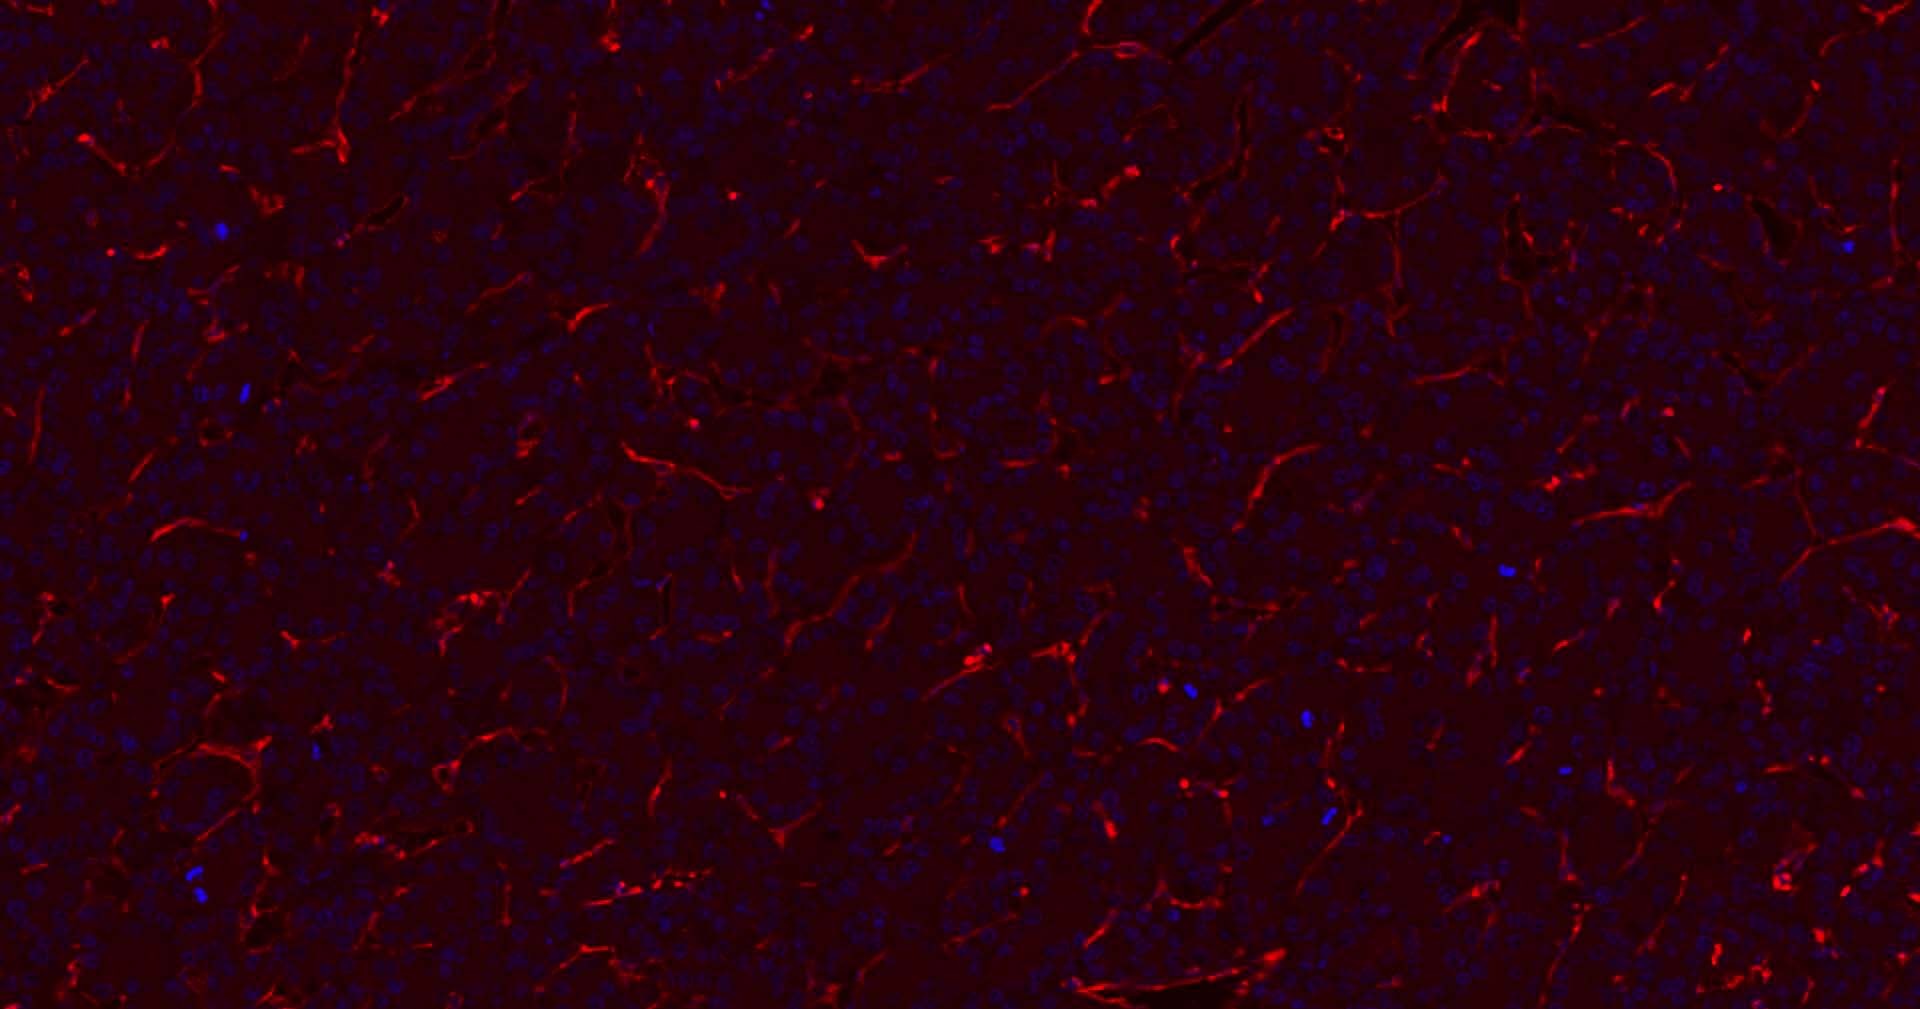

6. Paraformaldehyde-fixed, paraffin embedded Human Liver Cancer; Antigen retrieval by boiling in sodium citrate buffer (pH6.0) for 15 min; Antibody incubation with CD31 Monoclonal Antibody, Unconjugated (TMAB-00354) at 1:200 overnight at 4°C. Followed by conjugated Goat Anti-Rabbit IgG antibody (Red), DAPI (blue) was used to stain the cell nucleus.

7. Paraformaldehyde-fixed, paraffin embedded Human Colon Cancer; Antigen retrieval by boiling in sodium citrate buffer (pH6.0) for 15 min; Antibody incubation with CD31 Monoclonal Antibody, Unconjugated (TMAB-00354) at 1:200 overnight at 4°C. Followed by conjugated Goat Anti-Rabbit IgG antibody (Red), DAPI (blue) was used to stain the cell nucleus.